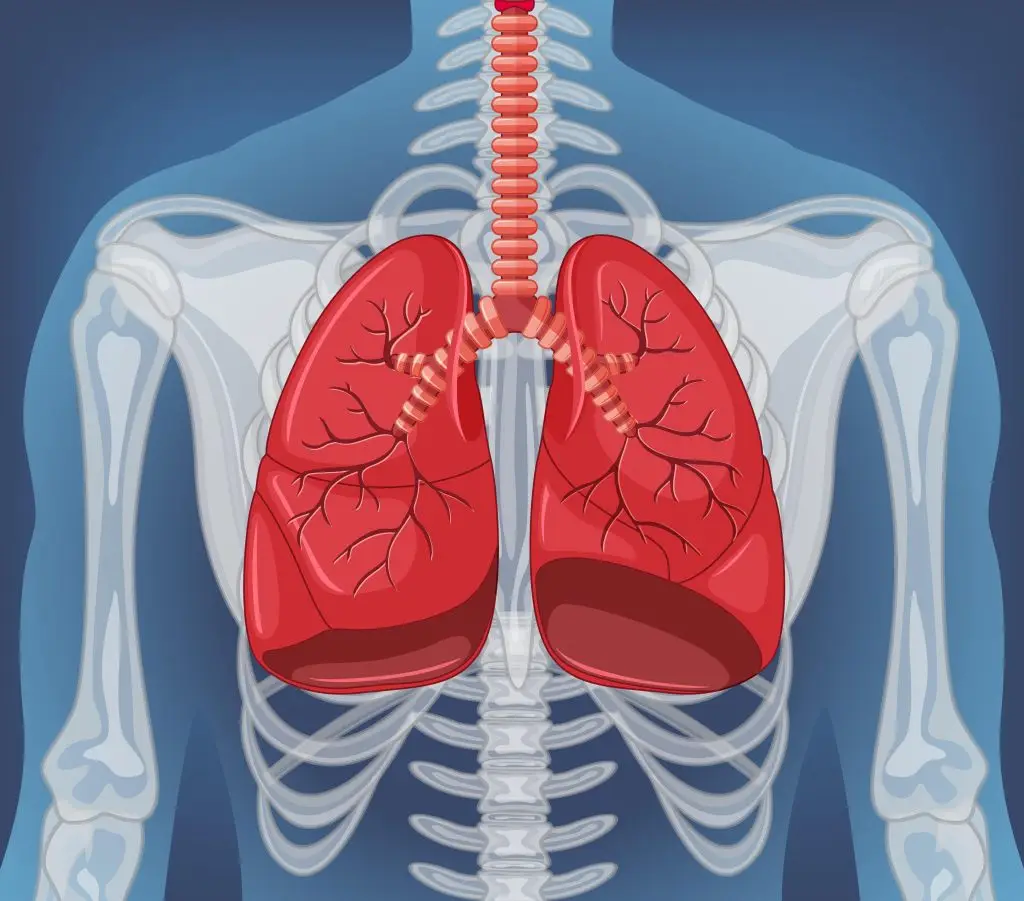

Bronchi

Large tubes air travels down to reach the lungs

Lungs

Bronchioles

Small branches of the bronchi; delivers air to the alveoli

Alveoli

Tiny air sacs of the lungs where gas exchange takes place

Diaphragm

Muscle sitting below the lungs that controls breathing

Carina

Location where the bronchi split into left and right